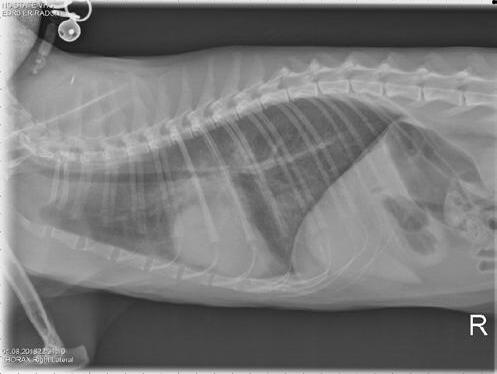

Radiography

This is the most appropriate imaging modality to diagnose/confirm CHF. The presence of oedema and/or pleural effusion, in addition to cardiomegaly, will confirm the diagnosis (Figure 7)